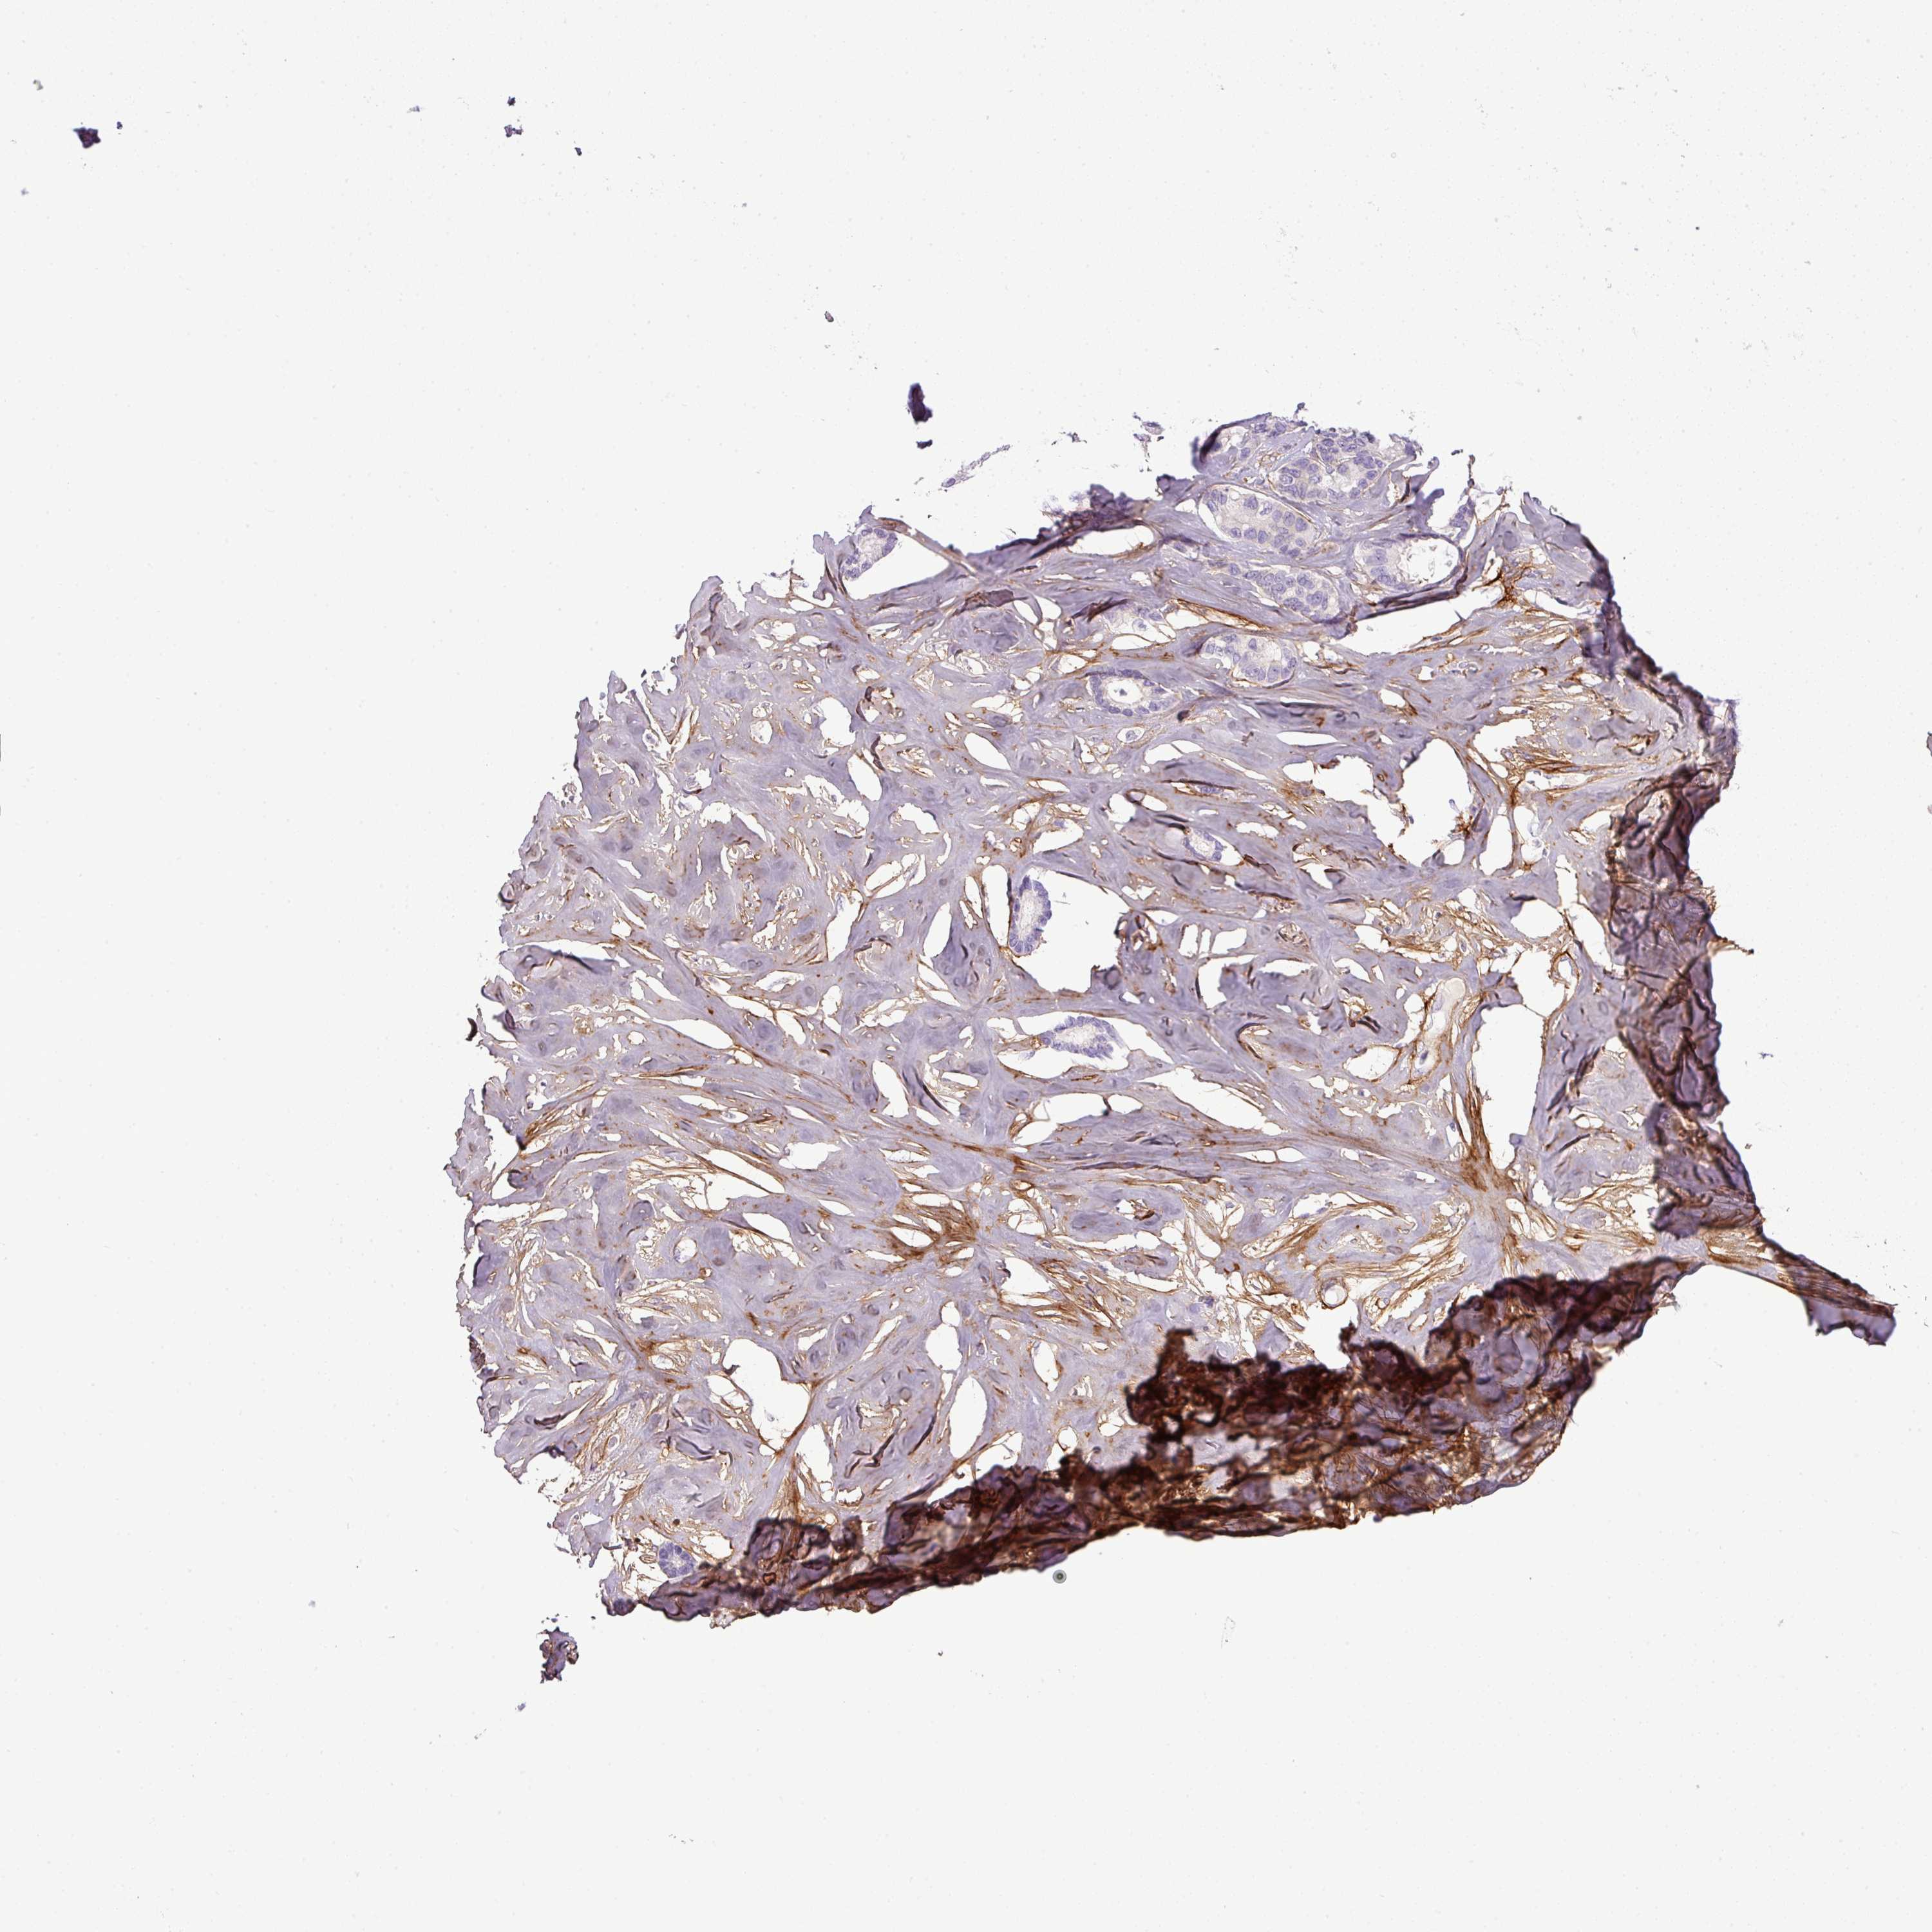

BRCA TCGA BRCA VALIDATION PROTEIN EXPRESSION

ANTIBODIES

AND

VALIDATION